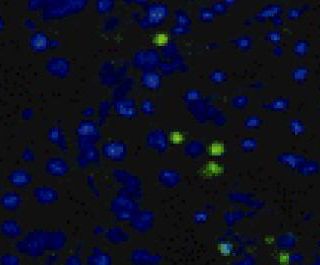

Previous studies have shown that the interaction of RNA and protein plays an important role in the formation of HIV virus particles...